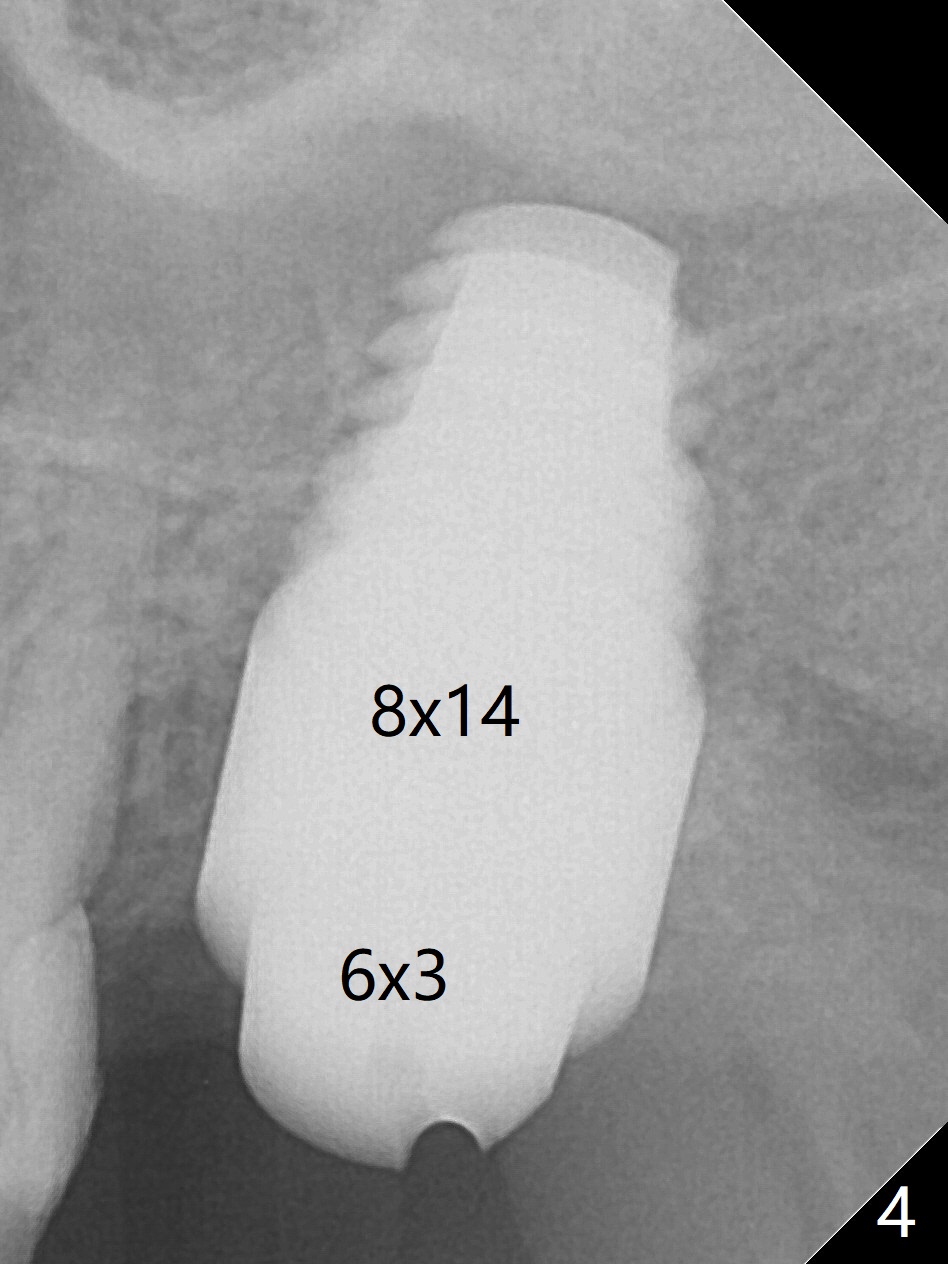

A 56-year-old woman has sign of periimplantitis 2 years 9 months post cementation. After incision, the 5.5x13 mm bone-level implant is ~ 3 mm inferior to the buccal crest. The implant is removed with 7/6 mm trephine bur, elevator and implant driver. The sinus membrane perforates. A 8x17 mm tap achieves stability (Fig.1), but the peripheral bone seems to be thin. Although a 7x14 mm tissue-level implant has stability, it is placed too deep (Fig.2). Following insertion of a piece of Osteogen plug for sinus membrane repair, a 8x14 mm implant is placed with >40 Ncm with allograft placed around the unpolished portion of the implant (Fig.3,4). A 6x3 mm abutment is placed to hold periodontal dressing in place. Because of the abutment with a slot (Fig.5 A), the periodontal dressing remains in place 4 days postop before the patient travels back home for 4 hours. In fact there is no postop sinus infection; the implant threads seems not be exposed 3 months postop (Fig.6). Because of the large implant, it is loaded early (Fig.7, 8 (Temp Bond)). Upper Molar Immediate Implant, Trajectory II 劈开术 Xin Wei, DDS, PhD, MS 1st edition 08/09/2019, last revision 04/11/2021